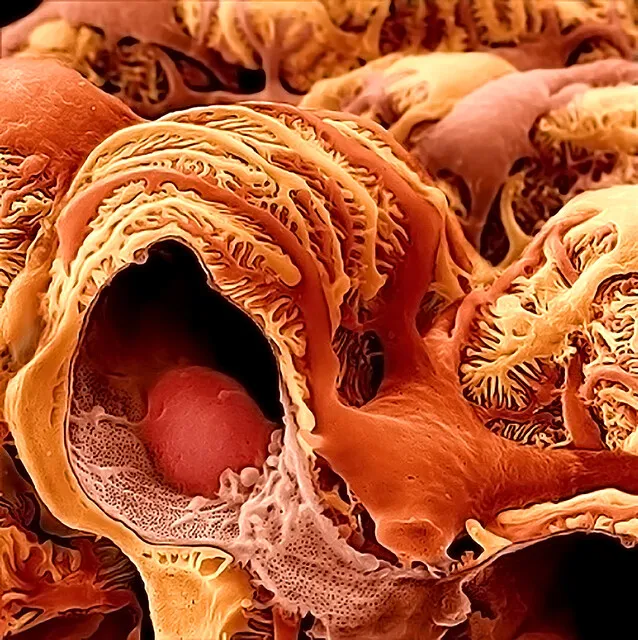

Você sabia que injeções cosméticas podem causar hipercalcemia e insuficiência renal anos após o procedimento? Descubra mais sobre os riscos e tratamentos dessa complicação em nosso novo post no blog!